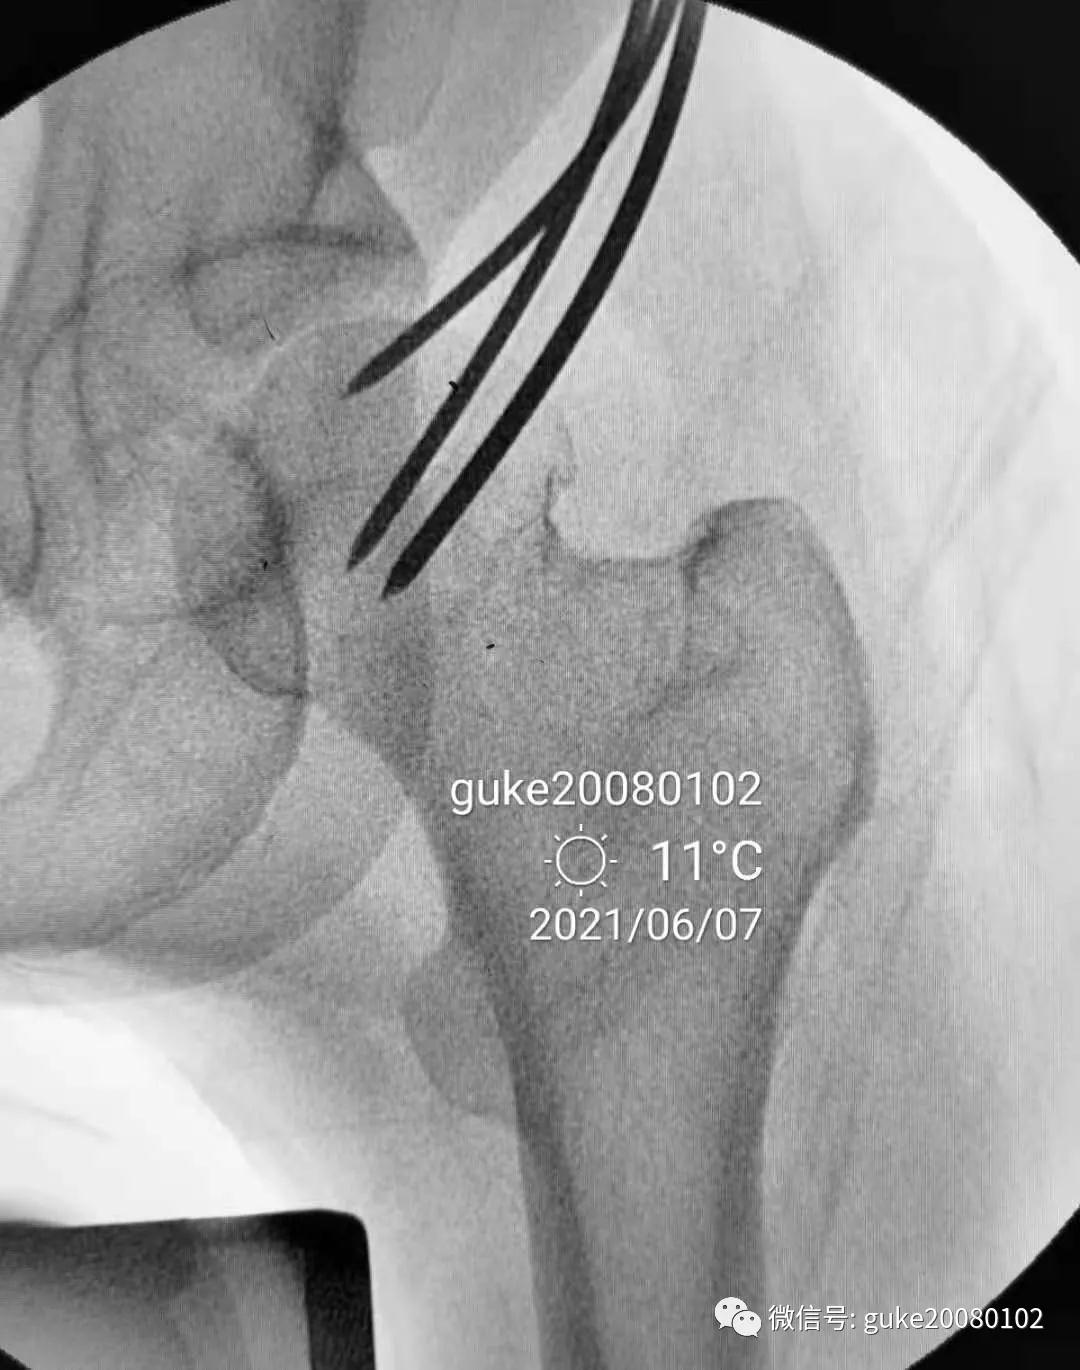

患者置于牵引床上,固定骨盆,尝试Ledbetter法复位,透视见复位不佳。骨折断端崁插,股骨头外翻。

- 在大转子顶点近端5厘米处,经皮向股骨头上方插入直径2.0mm克氏针两枚,敲击克氏针至骨质,撬拨头颈骨折块复位。

- 撬拨力量偏小,骨折复位不足。再插入一枚2.5mm克氏针,接力撬拨,骨折复位。